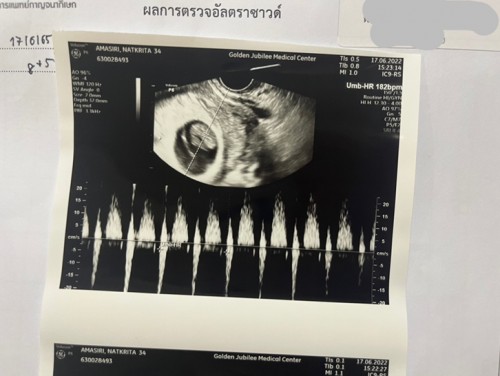

ทีม17มกราคม66จ้า บ้านนี้แพ้หนักมาก ไปซาวด์ตอนน้อง9wค่ะแม่